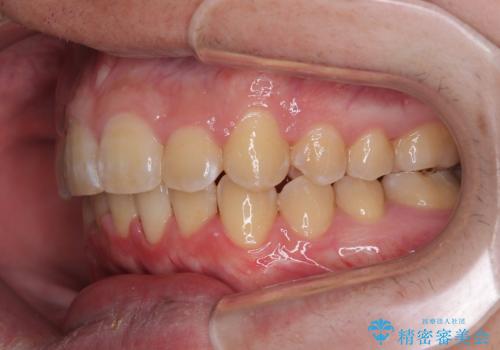

上下前歯にデコボコがありましたが、特に上顎の叢生が強く、通常に歯列を整えると、上顎が前方に突出し、口元の突出感が残った仕上がりとなる可能性が考えられました。

補助装置を用いて上顎歯列全体を後方に移動させる力をかけ、唇が閉じやすいような仕上がりを目指して、ワイヤー装置にて矯正治療を行うこととしました。

非常に咬合力が強く、左側の臼歯がなかなか後方へ移動できなかったのですが、2年ほどかけて大変満足のいく仕上がりを達成することができました。